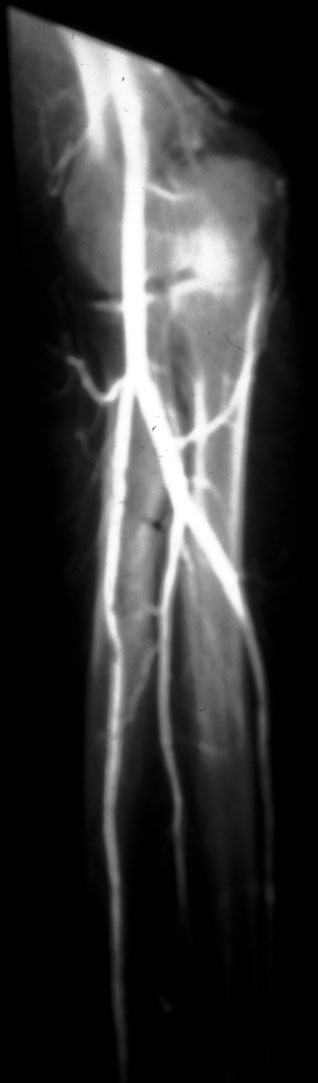

AP Brachial Angiogram -- Identify arteries: brachial, radial, ulnar, common

interosseous, ulnar recurrent, radial recurrent